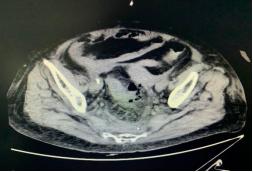

女性,78岁,因“上腹部疼痛不适伴腹泻1天”入院。患者1天前无明显诱因出现上腹部疼痛,伴有腹泻,外院查CT示乙状结肠穿孔(图2-1),以“乙状结肠穿孔”入院;体格检查提示腹胀明显,腹部压痛(+),无反跳痛;血常规示中性细胞比率 93.74%、超敏C反应蛋白 323.48mg/L、总蛋白 58.5g/L、白蛋白 33.3g/L、降钙素原 9.77 ng/L、B型钠尿肽前体12537 pg/mL;建议急诊行手术治疗,患方拒绝,要求保守治疗,后转入ICU监护治疗,治疗后无明显好转,病情进一步加重,出现高热、血压下降等感染性休克症状;急查肠镜示乙状结肠穿孔(图2-2),与患者家属进一步沟通后行剖腹探查术;术中探查见乙状结肠可见1×1cm大小穿孔,肠壁颜色紫黑,表面附着大量脓苔,腹腔可见大量血性腹水(约500ml),遂决定性行横结肠造口+腹腔引流+乙状结肠穿孔修补术,术程顺利。术后予以禁食、肠外营养支持、抗感染、肠菌灌肠治疗等,1月后肠功能逐渐恢复、能进食半流饮食,出院。

图2-1 CT示乙状结肠穿孔